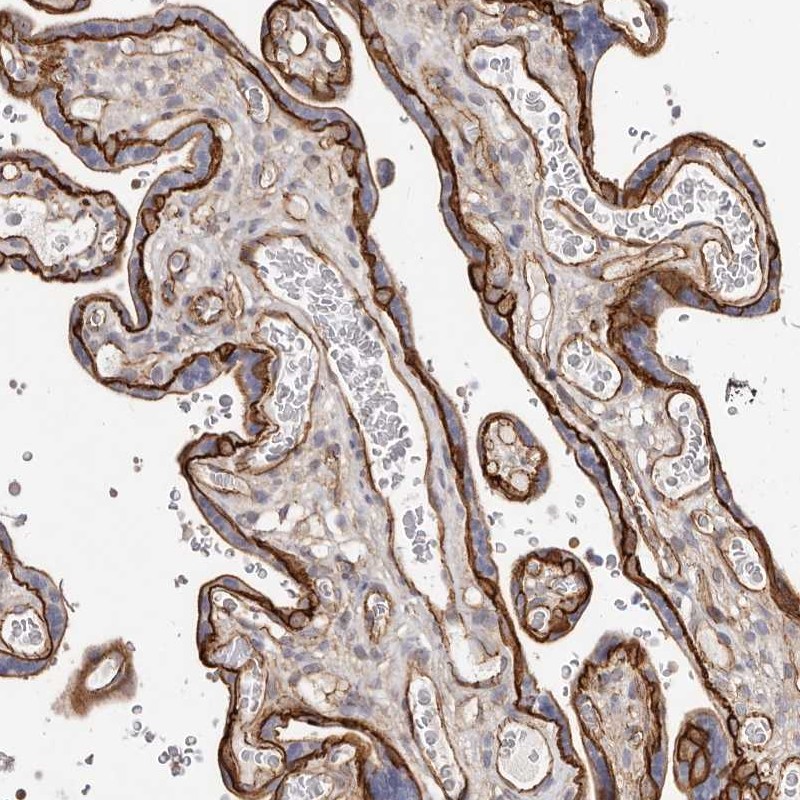

Immunohistochemistry analysis in human placenta and skeletal muscle tissues using Anti-CTNNB1 antibody. Corresponding CTNNB1 RNA-seq data are presented for the same tissues.